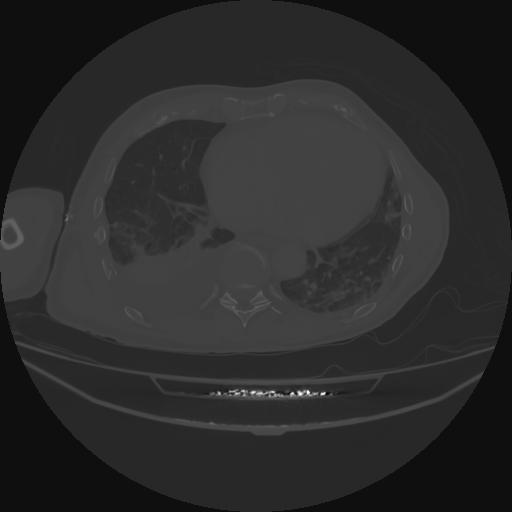

5 CUERPO,CE,Vol,1.0,CUERPO,,